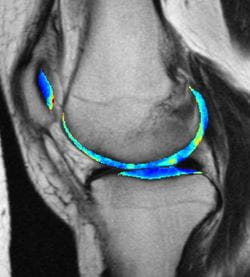

For this study, the researchers looked at knee MRIs from the Osteoarthritis Initiative, which followed thousands of people for seven years to see how osteoarthritis of the knee develops. They focused on a subset of patients who had little evidence of cartilage damage at the beginning of the study.

In retrospect, we now know which of these participants went on to develop arthritis and which didn’t, and the computer can use that information to learn subtle patterns on the MRI scans of presymptomatic people that are predictive of their future osteoarthritis risk.

“When doctors look at these images of the cartilage, there isn’t a pattern that jumps out to the naked eye, but that doesn’t mean there’s not a pattern there. It just means you can’t see it using conventional tools,” said lead author Shinjini Kundu, MD, PhD, who completed this project as part of her graduate training in the Pitt Medical Scientist Training Program and Carnegie Mellon Department of Biomedical Engineering.

Overall, the algorithm predicted osteoarthritis with 78% accuracy from MRIs performed three years before symptom onset.